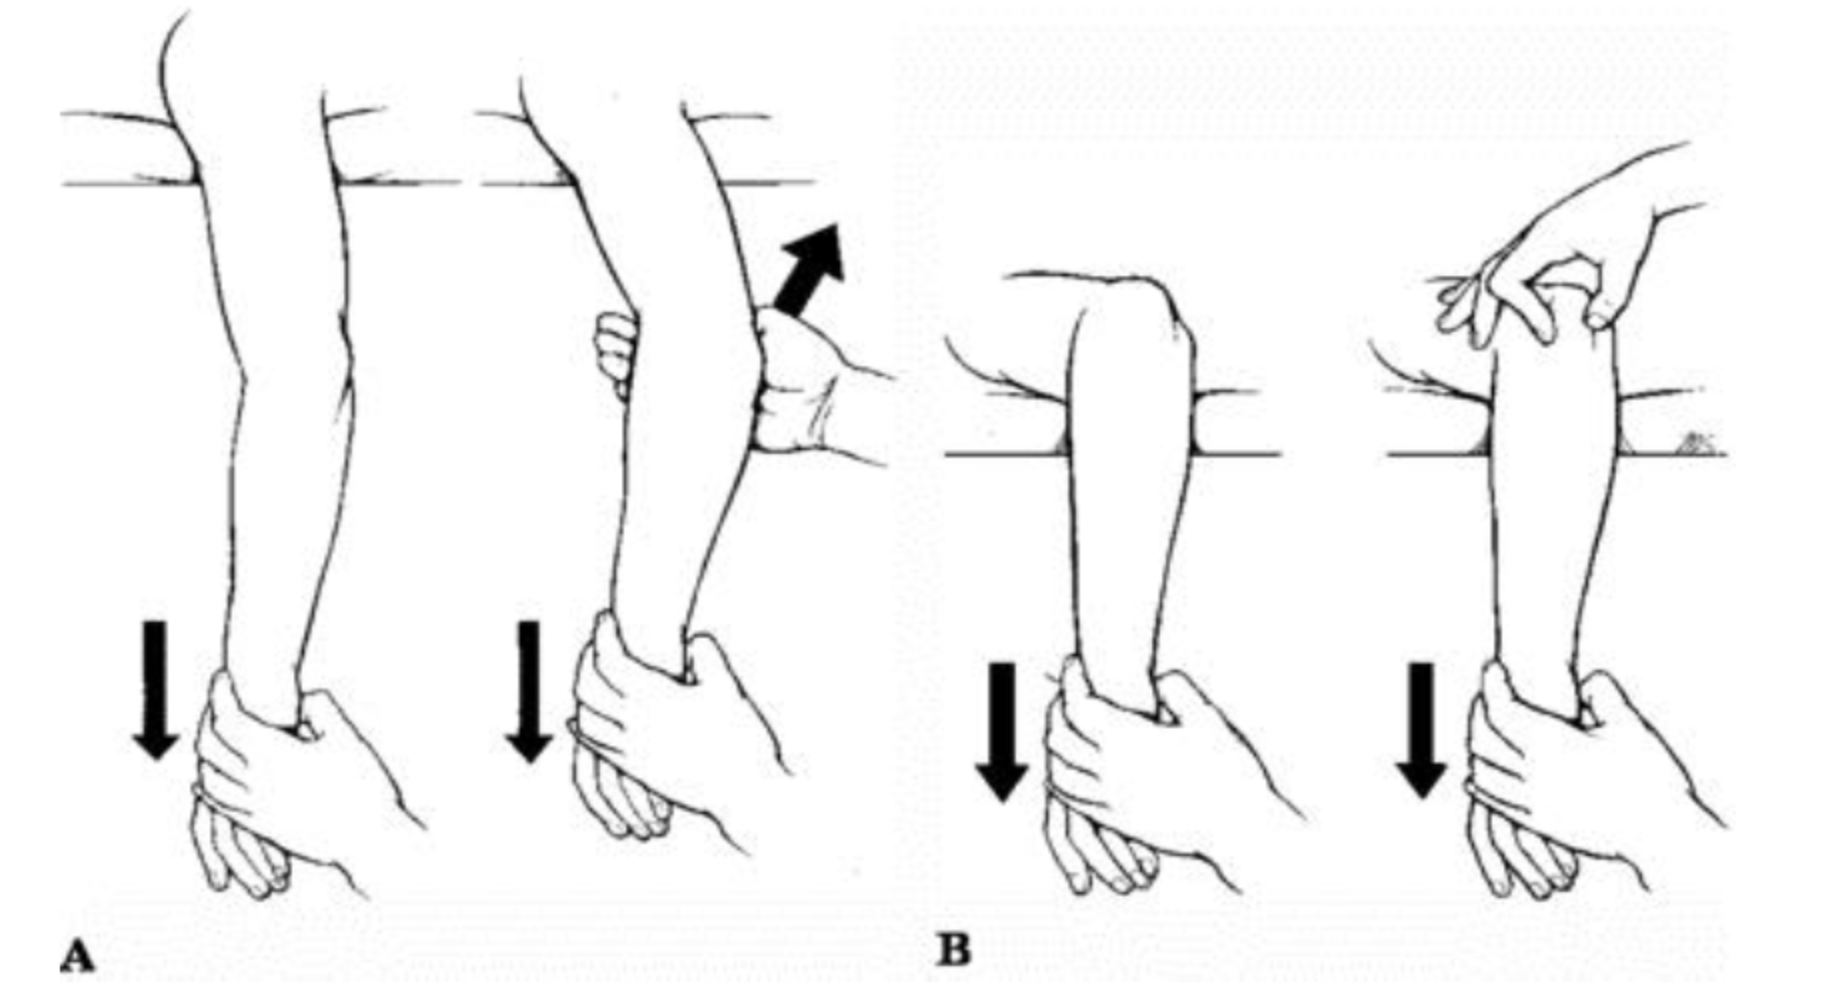

If this is performed externally, that is, without opening the arm, it is known as closed.

Caution can help reduce your risk of a dislocated elbow. The act of restoring alignment to the elbow is called a reduction maneuver. Types of reduction of elbow dislocation first aid immediately after the injury you should put.

Listen for a click or a palpable pop at the radial head, which. A gentle pull and push and the elbow could be back in place. Often, in addition to a dislocation, there is a fracture with displacement of bone fragments, etc.

In this video we treat a patient with a posterior elbow dislocation. It is done gently and slowly. Ad browse & discover thousands of brands.